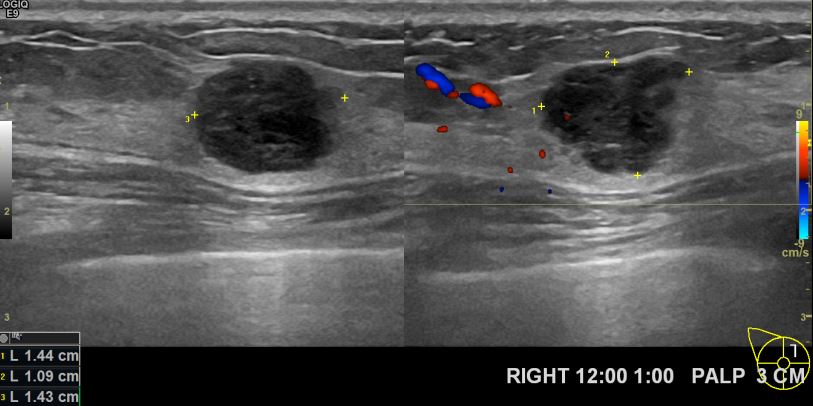

상기환자 우측유방에 만져지는 멍울이 있어 내원하시신 30대 여성분으로 초음파검사후 우측유방에 의심스러운 멍울 조직검사후 유방암진단되었읍니다.빠른 쾌유를 바랍니다.